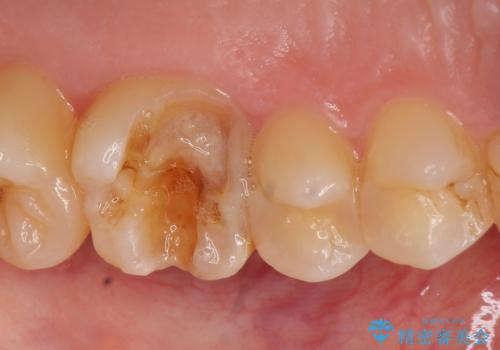

- 左上の奥歯が痛んでものを食べられないといらっしゃった方の症例です。

左上6は虫歯を除去後、神経症状がないことを確認し、オールセラミッククラウンによる補綴を行いました。

左上5は古い樹脂と虫歯を除去後、セラミックインレーによる修復を行いました。